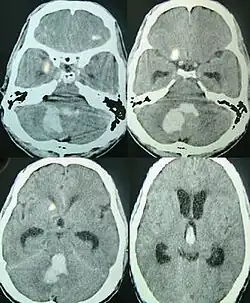

![]() | |

| CT scan of a spontaneous intracerebral bleed, leaking into the lateral ventricles | |

Intraparenchymal hemorrhage can be recognized on CT scans because blood appears brighter than other tissue and is separated from the inner table of the skull by brain tissue. The tissue surrounding a bleed is often less dense than the rest of the brain because of edema, and therefore shows up darker on the CT scan.[31] The oedema surrounding the haemorrhage would rapidly increase in size in the first 48 hours, and reached its maximum extent at day 14. The bigger the size of the haematoma, the larger its surrounding oedema.[32] Brain oedema formation is due to the breakdown of red blood cells, where haemoglobin and other contents of red blood cells are released. The release of these red blood cells contents causes toxic effect on the brain and causes brain oedema. Besides, the breaking down of blood-brain barrier also contributes to the odema formation.[13]